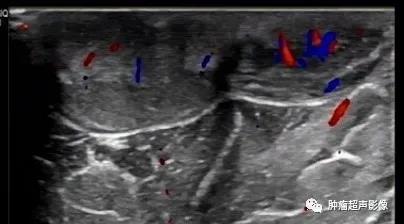

病理证实的隆突性皮肤纤维肉瘤:上臂隆起于皮肤表面的无痛肿块,呈紫红色,形态不规则,水平方向生长,内回声不均(见不规则条带状高回声与低回声相间隔),血流稍丰富。